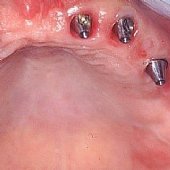

Bilder: Zahnimplantate bei Zahnlosigkeit im Oberkiefer

• Zahnloser Oberkiefer mit ausreichend Knochen Weichgewebe.

• Implantate eingesetzt mit Durchtrittspfosten zur Aufnahme der Brücke.